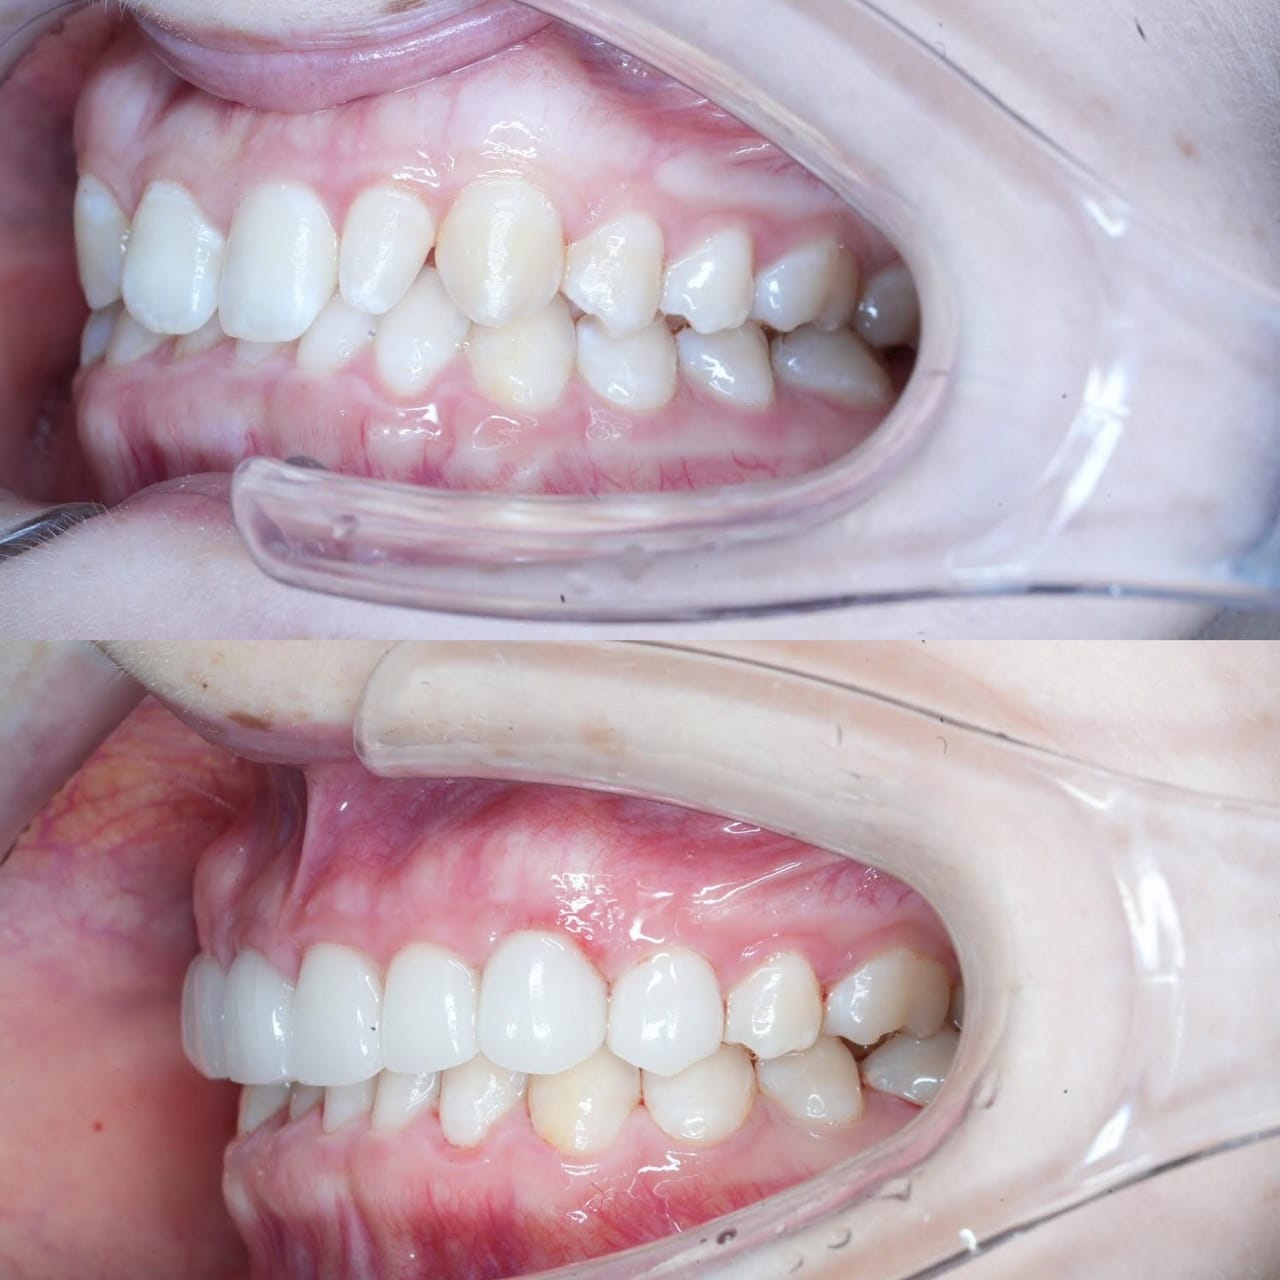

Case013

お医者様の患者様です。

「上下額前突、歯の傾斜が出ていて口元が出てしまっている」ことが主訴の患者様の症例です。

歯の大きさも気にされており、小さくしながら色も綺麗にしたいということでセラミック矯正をご提案しました。

治療の結果、口元が下がることで閉口筋が活発になり、お顔の印象も変わりました。

【治療回数】

3回(初診カウンセリング含む)

【治療期間】

3週間

担当 理事長 佐藤悠野